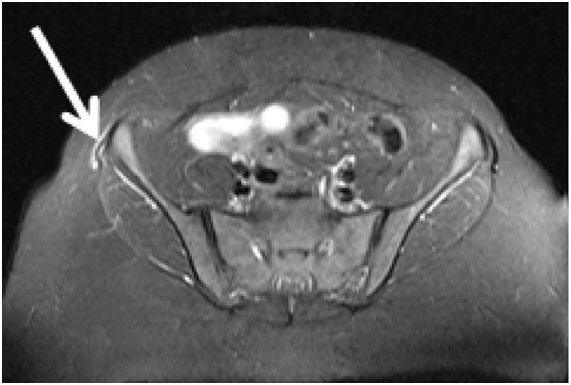

37-year-old woman, obese, with pain in the right hip, close to the iliac spine for 06 months, worsening at night. Works as a clerk and walks about 6 kilometers daily. Deny other traumas and physical activity. At physical examination, the patient reported pain on palpation of the iliac tubercle on the right and positive test on Ober's maneuver. Ely test and contracture test of the posterior thigh muscles negative. No edema or bruising at the site of pain inspection. MRI demonstrated swelling around the right anterior iliac spine and sign change of the iliotibial band inserting, compatible with proximal iliotibial band syndrome (Figures 1 & 2). With the diagnosis, the patient was advised to perform rest, treatment with anti-inflammatory and physical therapy - shock wave therapy and muscle strengthening, in addition to diet for weight loss.

Figure 1 MRI T2 FAT SAT in coronal section in A and B demonstrating edema around the anterior superior iliac spine and high signal in the right ITB, compatible with the proximal iliotibial tract syndrome (white arrow).

MRI demonstrates signal increase in T2 STIR sequences around the insertion of the iliotibial band in the iliac tubercle and may also show partial thickening and / or partial rupture of its proximal insertion.4 Bone edema of the iliac tubercle is uncommon.4 All patients reported in the literature responded to resting and physiotherapeutic treatment for stretching and muscle strengthening of IBT, in addition to anti-inflammatories.1,4